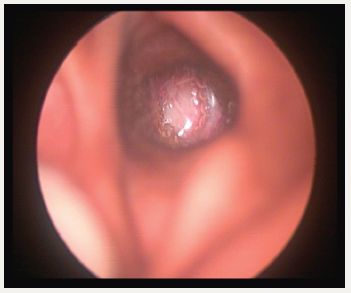

Persistent fluid in the middle ear causes not only reduced hearing, can go in for poor scholastic performances, speech-language development also. In long standing effusion, structural damage of the tympanic membrane (T.M) can go in for atelectasis, adhesion, ossicular damages, retraction pocket, and finally cholesteatoma. Stuart Mawson had described many of these complications after a long term follow up 129 glue ear cases [2]. Auto inflation and treatment URTI is the only treatment required. But the child should not sniff in. He should learn how to blow the nose correctly by occluding ne side first and then the other side, not two sides together (Figure2). Otovent is a rounded plastic balloon with a plastic nose piece. When the balloon is inflated auto inflation take place [3]. Even though the condition is considered self-resolving, since URTI is very frequent in childhood, by the time one incidence of OME is coming down, another URTI may start and the middle ear goes back to the previous stage. OME being a silent condition, many of the children present only in the late stages of the spectrum of the disease. By that time, irreversible damages might have taken place. Experimental studies in Chinchillas have demonstrated that the relationship between the time of evolution of effusion and structural changes of mucoperiosteum are related [4]. In this context, we should regularly follow up patients who are having OME and likely to have OME because of very frequent URTI (Figure3). If there is a structural damage tympanostomy must be done. Further episodes of URTI must be treated promptly (Figure4). The update of guidelines points out that under the age of 4 years adenoidectomy must be combined only in children having nasal obstruction or chronic adenoiditis. Above 4years adenoidectomy can be combined. It is learned that earlier, there was an epidemic of tympanostomy in U.K. [5].

Figure 3:Adhesive otitis media.